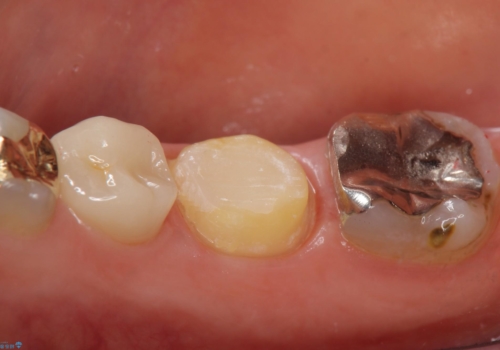

- 右下でものを咬むと歯茎が疼くので診て欲しいといらっしゃった方の症例です。

診査の結果右下6の歯の神経が死んでいたため、根管治療を行いました。

その後症状の消失を確認し、オールセラミッククラウンによる補綴を行いました。